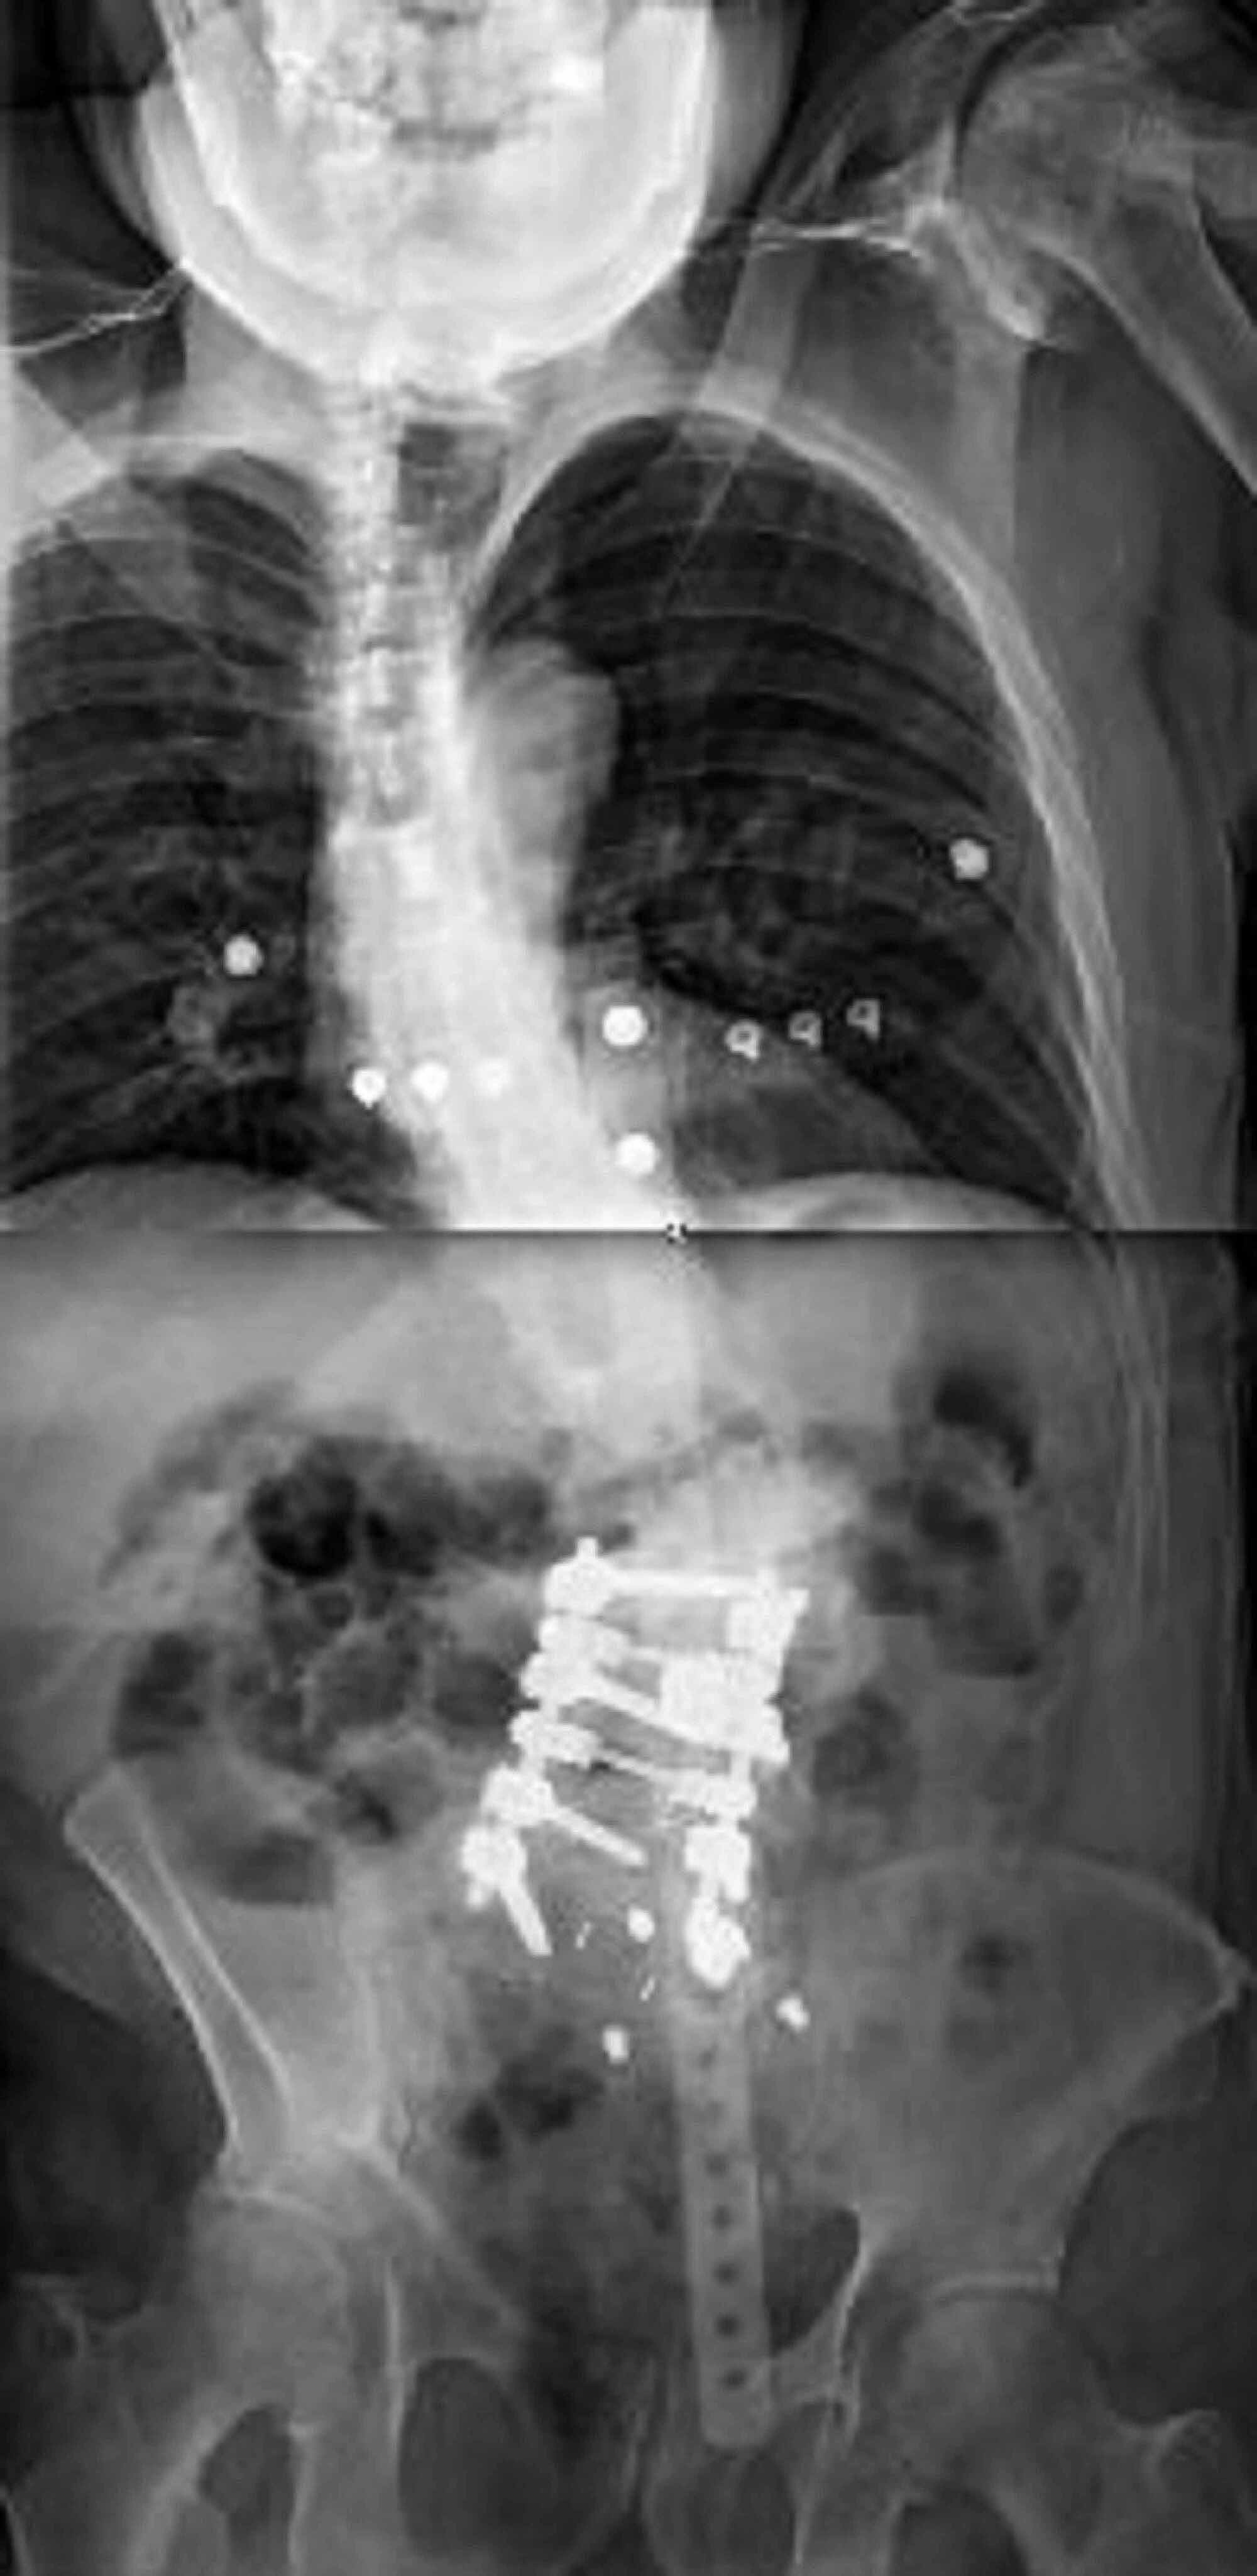

Radiographs demonstrating the application of the kickstand rod Kick Stand Rod This technique was found to provide. Only few studies about the coronal alignment correction with the kickstand rod were reported in the literature, until now. The aim of the present. This study tested the hypothesis that the kr technique provides. New surgical procedure for correction of coronal imbalance (ci) in spinal deformity patients. The objective of this study was to. Kick Stand Rod.

Case 4. This is a case of Type 2 CM. The kickstand rod technique Kick Stand Rod Only few studies about the coronal alignment correction with the kickstand rod were reported in the literature, until now. The kickstand rod technique is safe and effective for the correction of ci in spinal deformity patients. The objective of this study was to describe and evaluate a new surgical procedure for the correction of coronal imbalance (ci) in. The aim. Kick Stand Rod.

Radiographs demonstrating the application of the kickstand rod Kick Stand Rod This study tested the hypothesis that the kr technique provides. New surgical procedure for correction of coronal imbalance (ci) in spinal deformity patients. The kickstand rod technique is safe and effective for the correction of ci in spinal deformity patients. The kickstand rod technique has been described as a novel technique for cm correction using an accessory rod on the.. Kick Stand Rod.

Radiographs demonstrating the application of the kickstand rod Kick Stand Rod The kickstand rod (kr) technique is powerful for correcting truncal shift. The kickstand rod technique is safe and effective for the correction of ci in spinal deformity patients. This study tested the hypothesis that the kr technique provides. This technique was found to provide. New surgical procedure for correction of coronal imbalance (ci) in spinal deformity patients. The kickstand rod. Kick Stand Rod.